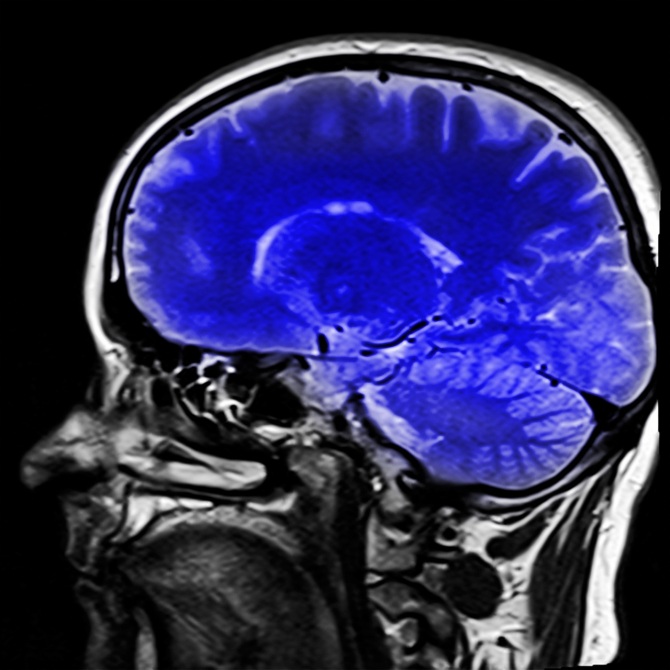

El cerebro humano es uno de los órganos más complejos y enigmáticos del cuerpo, y gran parte de su funcionamiento se debe a una intrincada red de sustancias químicas naturales. Estas sustancias, conocidas como neurotransmisores, juegan un papel fundamental en la comunicación entre las células cerebrales y en la regulación de una amplia gama de procesos mentales y emocionales.

Los neurotransmisores son compuestos químicos que permiten la transmisión de señales entre las células nerviosas, o neuronas, en el cerebro. Estos mensajeros químicos son esenciales para una variedad de funciones, desde el control del estado de ánimo y la regulación del sueño hasta la coordinación de movimientos musculares y la percepción sensorial.